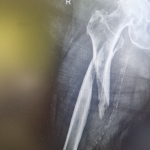

Zabiegi

Moja praca w RTG

Miednica i kończyna dolna